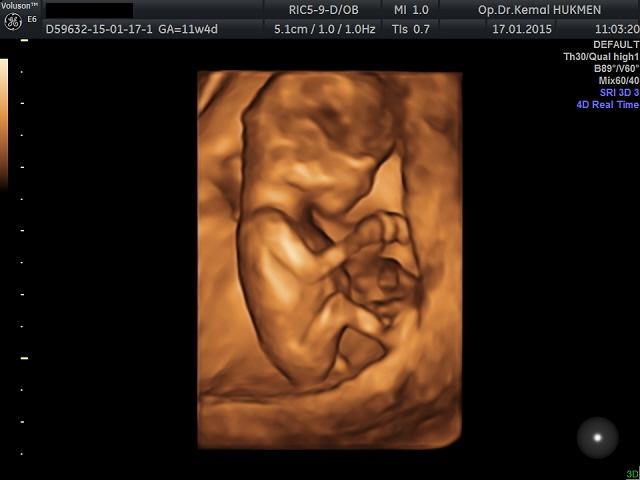

Kemal hükmen kadın hastalıkları doğum uzmanı hd live 3d 4d ultrason gebeli̇k taki̇bi̇ bebek sahi̇bi̇ olamama kizlik zari tami̇ri̇.